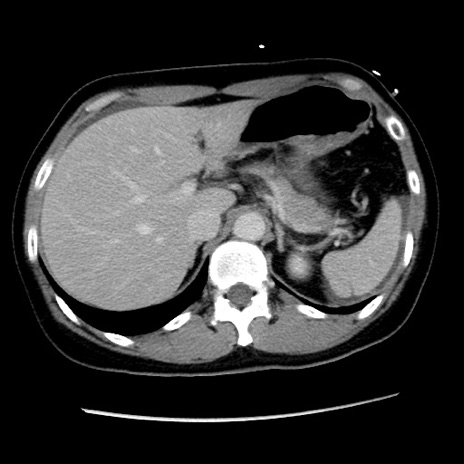

症例10(横断像)

【症例】 50歳代女性

【主訴】 腹痛

【現病歴】前日生レバーを食べた。今朝に排便あり。 昼前に突然発症の腹痛を生じ、当院救急外来を受診した。

【既往歴】 子宮筋腫にてで子宮全摘後

【身体所見】 意識清明、腹部:平坦、軟、下腹部やや左を中心に圧痛・反跳痛あり、筋性防御あり

【データ】WBC 7800、CRP 0.07